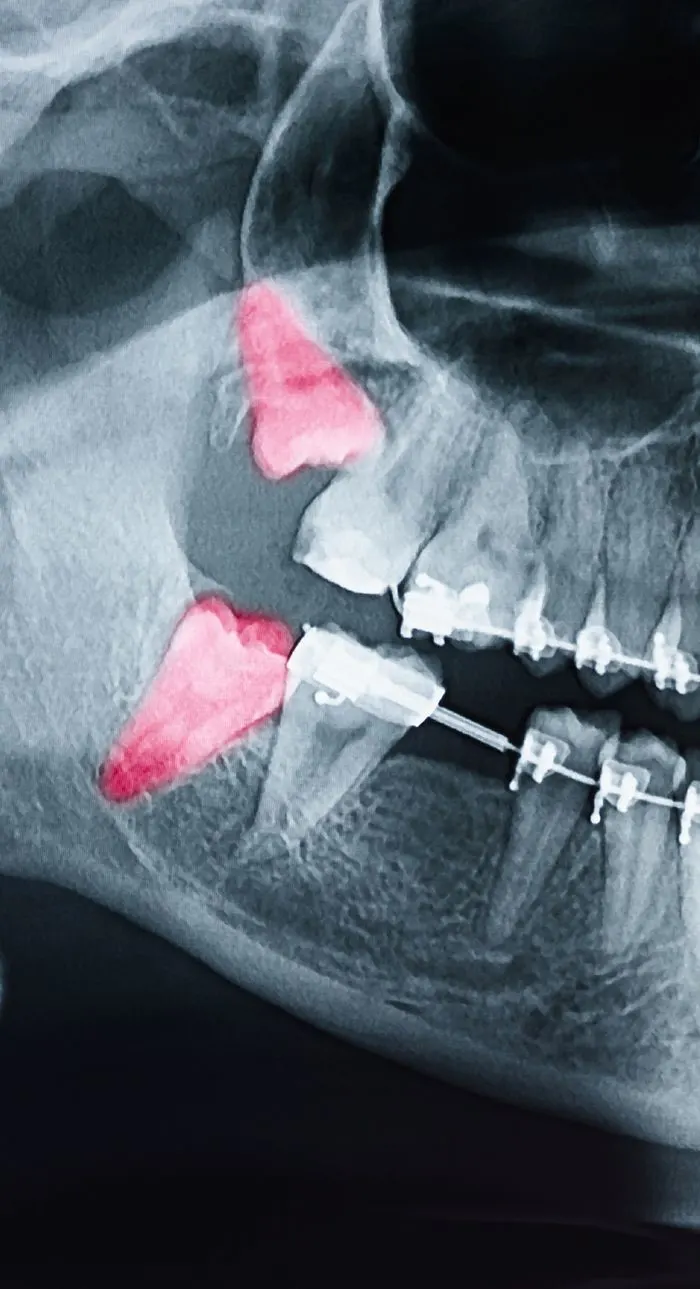

Problematic teeth negatively impact your overall oral health. Our team prioritizes preserving your natural teeth, but sometimes an extraction is the best way to save your smile. There are various reasons for needing a tooth extracted. Wisdom teeth often cause discomfort that can be relieved through extraction, and some advanced restorative procedures, like dental implants, require the removal of unhealthy teeth. Using gentle techniques and local anesthesia, tooth extractions can be quick and painless.

The most common reason for tooth extractions is improper wisdom teeth growth. If your dentist determines that your wisdom teeth are impacted or not erupting correctly, extraction may be recommended to protect the health of your other teeth. Not everyone requires wisdom teeth removal, so it’s important to consult your dentist to determine if yours pose a problem.